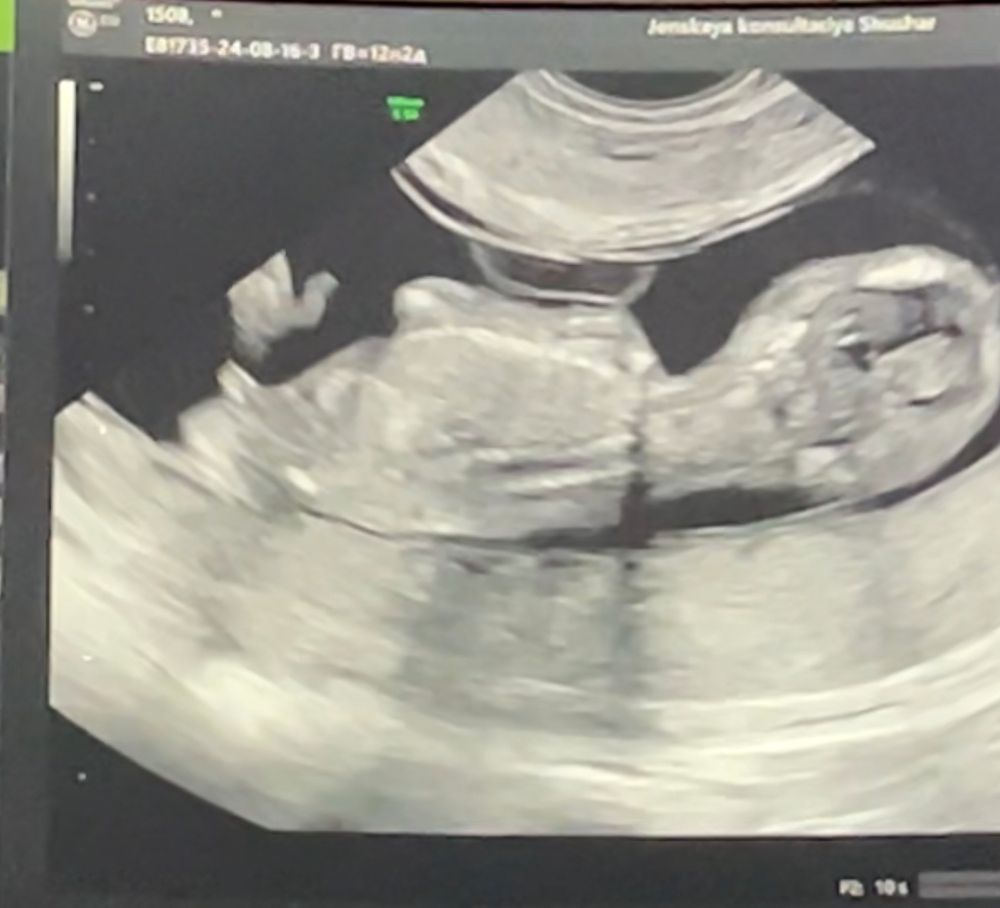

Мальчик или девочка?

Тест по крови определил Изображение мальчика

Мне мальчик виднеется, угол вроде как раз острый

Анастасия , на узи тоже Предположили мальчика

Надеюсь через несколько дней будет готов тест на выявление Y хромосомы. Муж мечтает о мальчике.